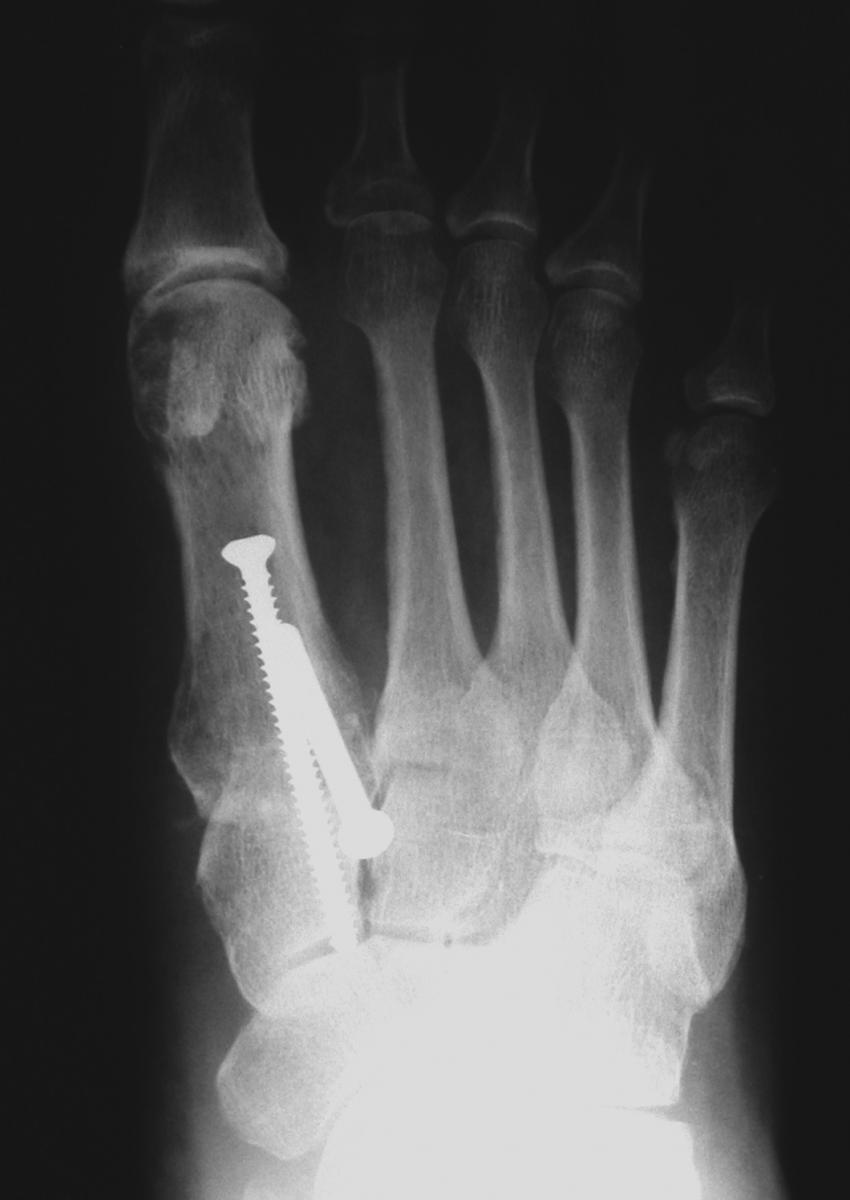

Does Early Weightbearing After Lapidus Increase Non-Union Risk?

Non-union can be a consequence of Lapidus arthrodesis but a recent study says allowing patients to bear weight early may not increase the risk of non-union.

The study, published in the Journal of Foot and Ankle Surgery, focused on 367 consecutive patients who had a unilateral modified Lapidus arthrodesis. Researchers categorized patients into early weightbearing (21 days or fewer) and delayed weightbearing (more than 21 days) groups. The study noted a total of 24 non-unions with 13 in the early weightbearing group and 11 in the delayed weightbearing group.

Dr. Bussewitz, a fellowship-trained foot and ankle surgeon who is in private practice in Iowa City, Iowa, says the post-op weightbearing protocol for the Lapidus bunionectomy is similar to that of other bunion procedures due to newer locking plate technology and application. He cites multiple studies that confirm locking plates as the most stable fixation construct for the Lapidus bunionectomy.

Traditionally, Dr. Bussewitz notes the first tarsometatarsal joint has been notorious for relatively high rates of non-unions. However, he says recent and upcoming studies point to improved joint preparation techniques and improved fixation techniques. Dr. Bussewitz says these developments “will likely lead to fusion rates for the first tarsometatarsal joint that are comparable to other, more predictable healing fusion sites.”

Dr. Hyer cites numerous studies demonstrating an equivalent if not better healing rate with early weightbearing in comparison to the reported healing rates of the traditional Lapidus technique. He emphasizes that surgeons must observe thorough and precise surgical techniques, and select a fixation construct that will withstand the stresses of early weightbearing.